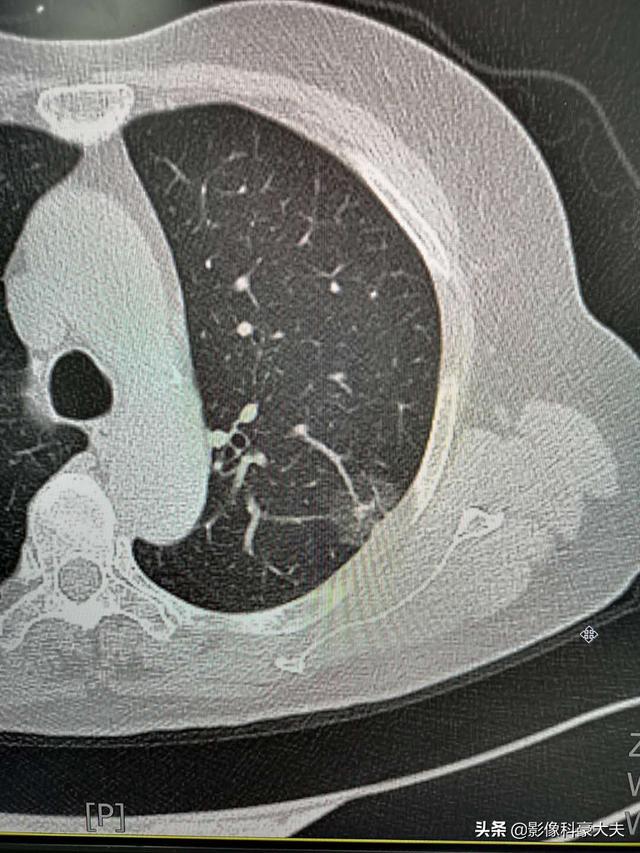

Ce vieil homme a également eu la chance d'être examiné pour une oppression thoracique, une toux et une faible fièvre, ce qui a permis de découvrir un adénocarcinome pulmonaire à un stade précoce sur le côté gauche.

Cet adénocarcinome précoce est curable, avec un taux de survie à 5 ans proche de 100 %, et il n'est pas trop tard pour repousser l'opération d'un mois ou deux.

Parce qu'elle a été détectée à temps, elle n'aurait pas évolué vers un cancer avancé.